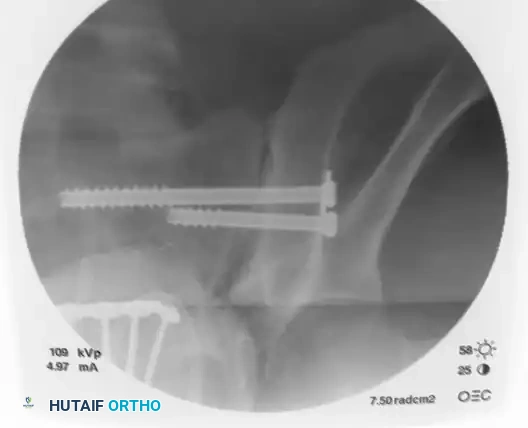

Image

On the lateral fluoroscopic view, place the tip of the guide on the exact predetermined starting spot. Once positioned correctly, impact the guide firmly into the iliac cortex using a mallet. This creates a stable docking point and prevents the guide from skiving along the curved iliac wing.